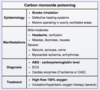

What is the likely diagnosis in a group of individuals that present with headache, nausea/vomiting, and confusion after eating at an indoor barbecue? Physical examination of one patient reveals tachycardia, tachypnea, and pinkish-skin hue.

Carbon monoxide poisoning

diagnosis is confirmed by measuring carboxyhemoglobin levels (> 3% in non-smokers; > 10% in smokers)